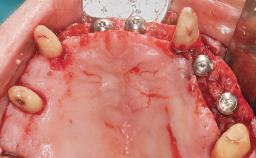

Conventional Loading of Eight Implants in the Maxilla and Final Restoration with a Full-Arch Gold-Ceramic FDP

A 35-year-old Caucasian female presenting with advanced periodontal disease involving both the maxillary and the mandibular dentition was referred for evaluation. The patient, a non-smoker in good general health, requested treatment for recurrent periodontal abscesses, tooth mobility, and discomfort during chewing, as well as restoration of her missing teeth with a fixed prosthesis to improve mastication and esthetics. All residual maxillary teeth exhibited plaque deposits, deep pockets, bleeding on probing, and class III mobility and were evaluated as hopeless. All residual mandibular teeth except tooth 37 could be maintained after periodontal therapy.

| Bone Augmentation | Horizontal|Staged|Vertical |

| Augmentation Materials | Autogenous block(s) |

| Soft Tissue Grafting | Staged |